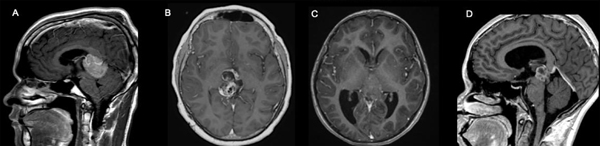

Es un tumor de grado intermedio (II-III) infrecuente que posee múltiples quistes, es heterogéneo y posee realce con contraste de los componentes sólidos y de las paredes quísticas. (Figura 1: D).

Es un tumor de alto grado (IV) con la capacidad de un crecimiento extenso (>5 cm), realce difuso con contraste, frecuente presencia de calcificaciones diseminadas con áreas quísticas asociadas. Presentan una elevada celularidad por lo cual restringen en difusión. Su propensión hacia la diseminación requiere una evaluación imagenológica completa del neuroeje. (Figura 1: C).

Es el tumor germinal de mayor frecuencia. Es de alto grado (IV) y posee una prevalencia mayor en el sexo masculino, es mayoritariamente sólido aunque puede poseer áreas quísticas. Suelen verse calcificaciones focales desplazadas o que envuelven a la glándula pineal. El componente sólido es hiperdenso en la TC de encéfalo y posee realce con contraste en la secuencia T1. (Figura 1: A).

Son tumores de distintos grados (I-IV) con mayor prevalencia en el sexo masculino y en pacientes menores a los 9 años. Suelen tener componentes sólidos y quísticos, con áreas de calcificación y tejido adiposo. (Figura 1: B).

Figura 1. Tipos Tumorales más frecuentes. A: Germinoma. B: Teratoma. C: Pineoblastoma. D: Tumor papilar.